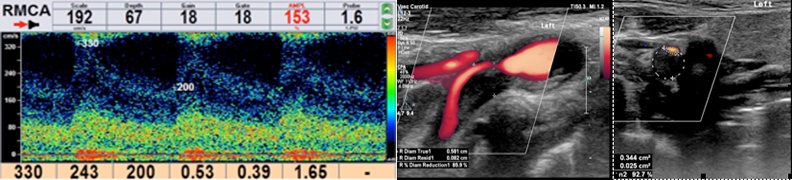

开展全脑血管造影、缺血性脑卒中急诊取栓、颅内外动脉慢性血管狭窄血管内开通手术(支架及球囊扩张)等手术。刁士元副主任医师已在我院成功开展全脑血管造影术和椎动脉支架植入术各1例。

左图:术前DSA提示左侧椎动脉V4段重度狭窄 ;

右图:支架植入后左侧椎动脉狭窄明显改善,术后TCD远端血流恢复正常